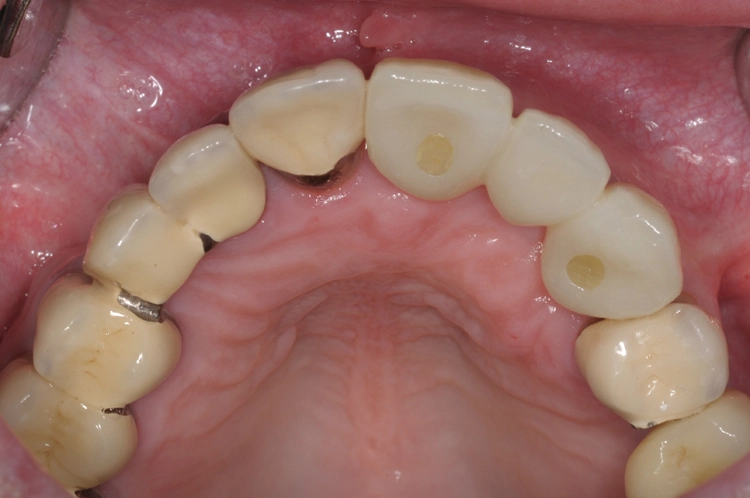

Ein 64 Jahre alter männlicher Patient ohne anamnestische Auffälligkeiten wurde mit dem Wunsch nach einer festsitzenden und ästhetisch ansprechenden Lösung im Frontzahnbereich von seinem Hauszahnarzt zur weiteren implantologischen Rehabilitation an unsere Praxis überwiesen. Nach eingehender klinischer Untersuchung wurde anhand einer 3D-Röntgenaufnahme mittels DVT das knöcherne Lager in der zu behandelnden Region beurteilt, worauf sich ein ausgeprägtes horizontales Knochendefizit zeigte, das eine Implantation in korrekter prothetischer Lage nicht zuließ (Abb. 1-3).

Die Entscheidung fiel daraufhin auf ein zweizeitiges Vorgehen mit vorheriger Knochenaugmentation in Schalentechnik und späterer Implantation von zwei BLT-Implantaten mit augmentativem Relining: Der Patient entschied sich nach ausführlicher Beratung und Vorstellung der alternativen Augmentationsmöglichkeiten für die Schalentechnik mit allogenen Kortikalisplatten und Granulaten (maxgraft® spongiosa, Straumann), wie die Abbildungen 4 bis 7 dokumentieren.